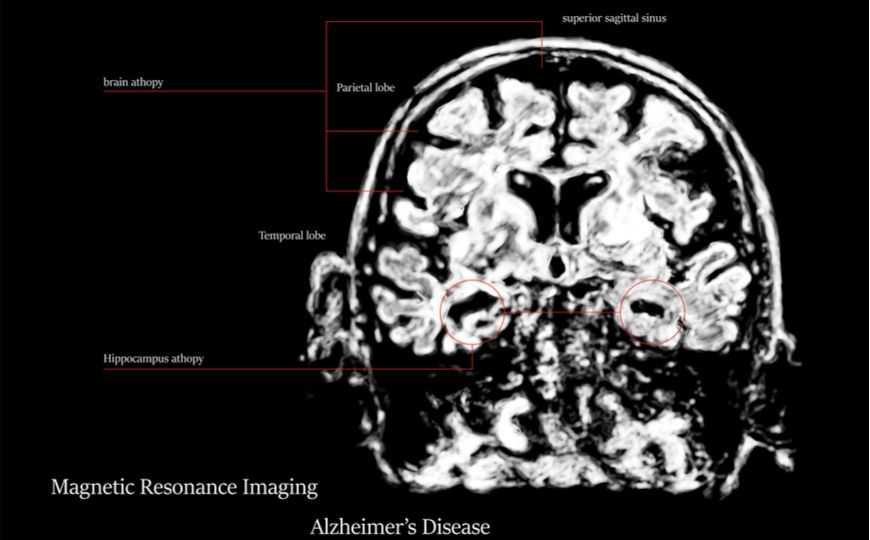

Болезнь Альцгеймера – тяжёлое и неизлечимое заболевание, связанное с накоплением в мозге нерастворимого комплекса, состоящего из протеолитических фрагментов белка – предшественника амилоида. Функция этого белка была установлена буквально только что, а вот борьба с амилоидом продолжается уже десятилетия и сталкивается со значительными трудностями. Поэтому любые новые данные о возможности терапии этого заболевания представляют большой интерес.